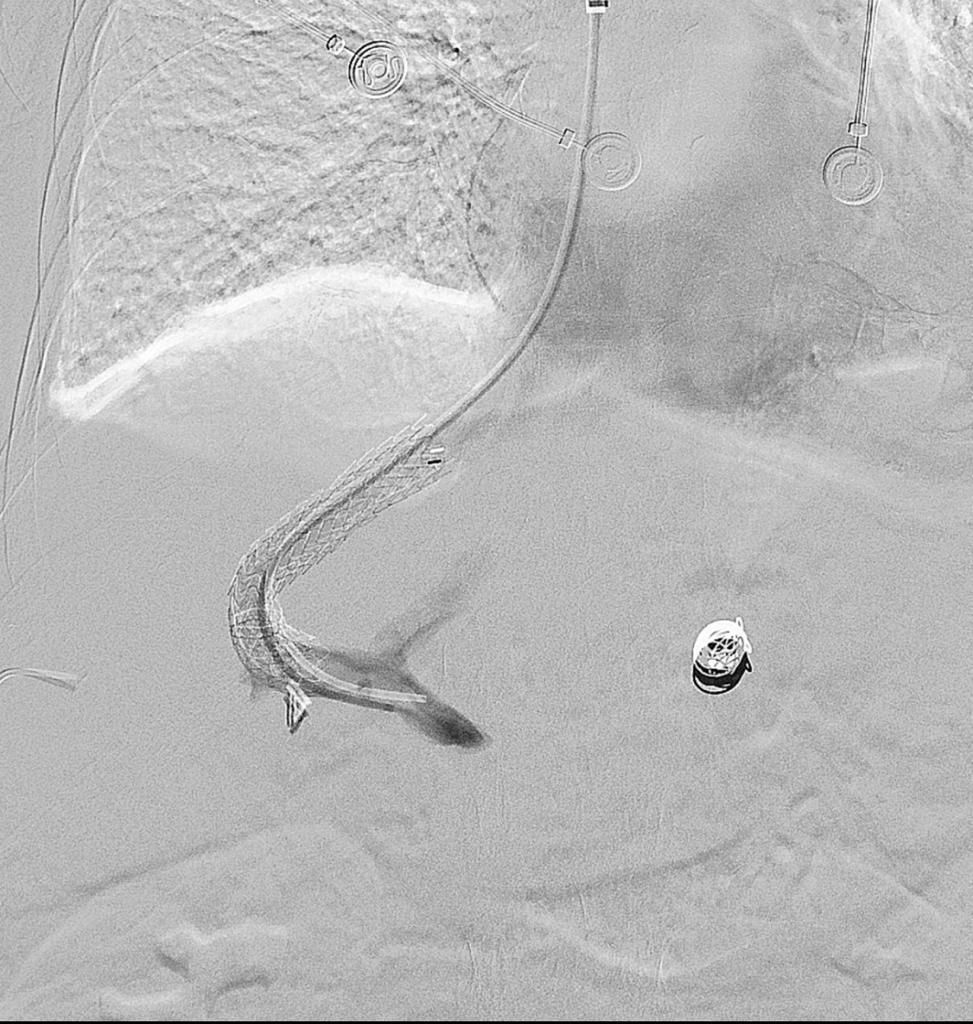

نجح فريق طبي و لأول مره بمستشفى شرق جدة في إجراء نادر من نوعه من إنقاذ حياة مريضة خمسينية كانت تعاني من تليف في الكبد و دوالي المريء و لديها نزيف متكرر يشكل خطراً على حياتها ، مما استدعى التدخل السريع ، حيث تم عمل وصلة وريدية بين الوريد الأجوف السفلي و الوريد الكبدي الأيمن عن طريق القسطرة ، و تم عمل الحالة بوحدة الأشعة التداخلية و القسطرة بالمستشفى من قبل استشاري الأشعة التداخلية و قسطرة الأوعية الدموية الدكتور أحمد سليمان كرسوع و بمساعدة فريق التخدير بالمستشفى .

و بفضل الله تكللت القسطرة التداخلية بالنجاح و غادرت المريضة في اليوم التالي و هي تتمتع بصحة جيدة .